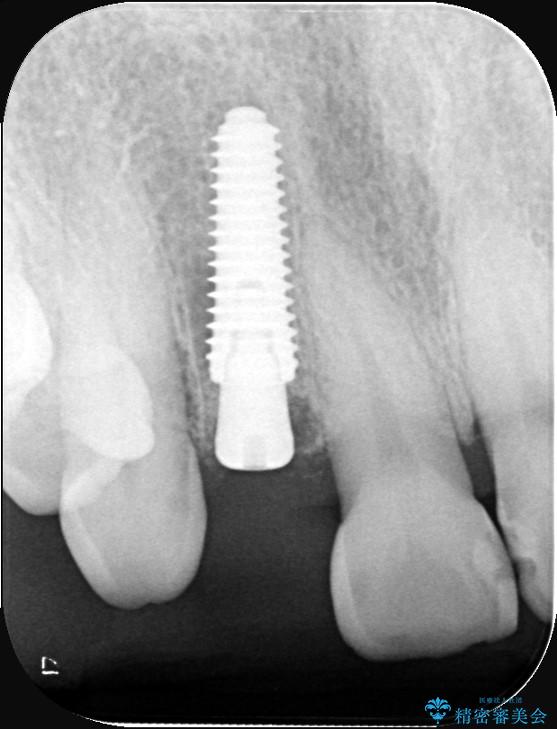

インプラント治療は、低侵襲で短期間に行える「抜歯即時インプラント治療」を選択しました。

この方法は、抜歯したその日にインプラントを埋入し、手術が1回で済むのが大きな特徴です。

治療期間も短く、抜歯からわずか3か月でオールセラミッククラウンを装着することができます。

また、オペ当日には仮歯まで装着するため、見た目を気にせず普段通りの生活を送ることができます。